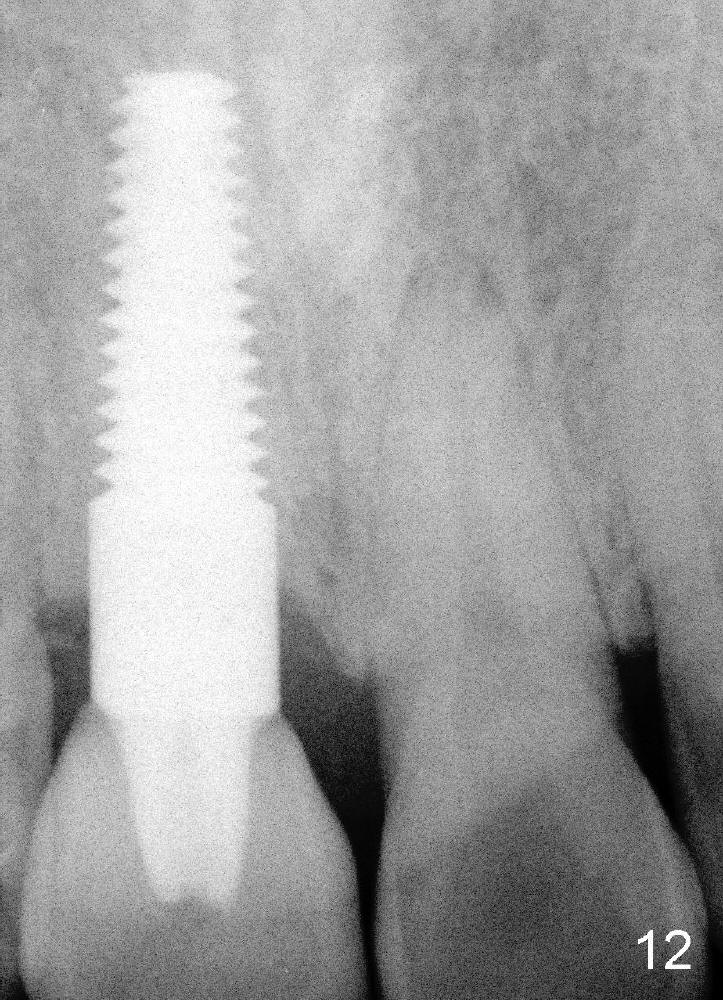

Fig.11,12 are taken 6,18 months post cementation, respectively.

When the patient returns 3 years 10 months post cementation, the tooth #9 fractures (Fig.13,15,16), and receives root canal therapy (Fig.14). The dark gingiva could be avoided if the implant is placed more palatally and smaller in diameter (Fig.15,16).